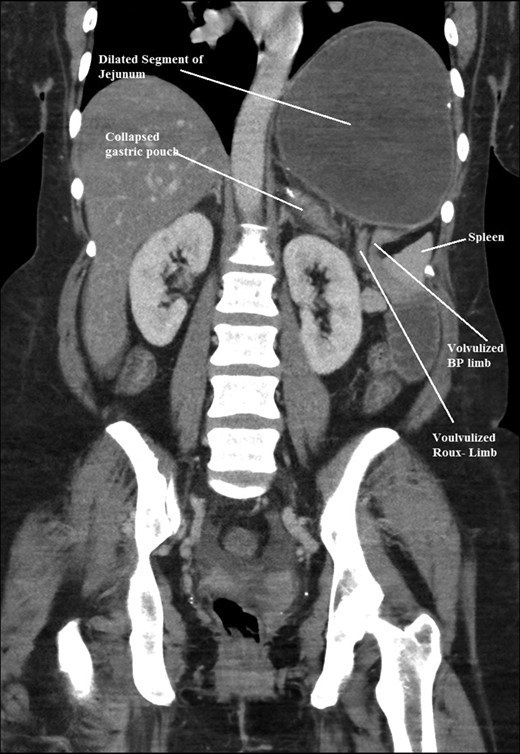

The intraoperative findings were not consistent with the radiological findings (Figs 1–4). As shown in the CT scan of abdomen and pelvis; multiple loops of dilated small bowel were seen, more predominantly dilated and matted bowel complex just above the spleen. The dilated bowel complex was decompressed using needle aspiration to help reduction of the bowel loops. The ileo cecal junction was then identified and traced back to the perisplenic hilar region. The trifurcation of three bowel loops (Roux limb, biliopancreatic limb and common limb) were identified with identification of ligament of Treitz. The prior gastric bypass was of ante colic- ante gastric type and Peterson’s defect was not closed. The above described bowel trifurcation had sunken postero- inferior to the spleen and had herniated through a potential space underneath the spleen and torsed around the splenic vessels and hilum. This picture was consistent with perisplenic small bowel volvulus. As noted earlier there was a massively dilated proximal small bowel segment above the spleen, displacing it caudally. Careful adhesiolysis was performed inferior to the spleen to release the segment of the trifurcation. The bowel segments once reduced were assessed and appeared viable. Of note, the spleen appeared better perfused after reduction. The remnant hernia defect of size 2 × 3 × 2.5 cm around the hilar region was then approximated using interrupted non-absorbable sutures. Enterotomy at the decompression site was closed with non absorbable suture. All potential sites of IH were re-examined and there was no evidence of any other internal herniation. Coelomic cavity was thoroughly irrigated and operation concluded successfully. Postoperative hospital stay was uneventful, and the patient was discharged home after two days.

Coronal CT scan of abdomen and pelvis showing Volvulized segment of bilio-pancreatic limb and its mesentery in the spleen hilum.